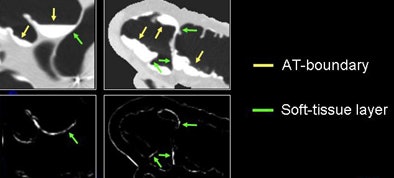

The next process is local roughness analysis, which is designed to determine whether the voxel being analyzed is on top of a thin soft-tissue structure between a tagged region and air (tagging-tissue-air layer), or an air-tagging boundary (AT-boundary), Yoshida said.

The surface of an AT-boundary is more irregular than a tagging-tissue-air layer because of local nonlinear volume averaging and/or semiliquid nature of the tagged fecal materials. Characteristics of the curvedness across scales can be used to differentiate the two types of boundaries.

"By using only the CT gradient, you're not able to differentiate them, but if you ... calculate the curvedness, which is essentially the curvature of the voxel, the AT-boundary has a different profile," Yoshida said.

Thus, the local roughness function measures the local surface irregularity to distinguish the structures. The local roughness response function enhances soft tissue in the tagging-tissue-air layer while suppressing the AT-boundary. As a result, "the soft-tissue density is preserved by applying this approach, and the AT-boundary is eliminated," Yoshida said.

| Local roughness analysis is designed to determine whether a voxel is part of a thin soft-tissue structure between a tagged region and air (tagging-tissue-air layer) or an air-tagging boundary (AT-boundary). The surface of an AT-boundary is more irregular than that of a tagging-tissue-air layer due to local nonlinear volume averaging and/or the semiliquid nature of the tagged fecal materials. Characteristics of the curvedness across scales can be used to differentiate the two types of boundaries. The local roughness function measures the local surface irregularity. Application of the local roughness response enhances soft tissues in the tagging-tissue-air layer and suppresses the AT-boundary. |